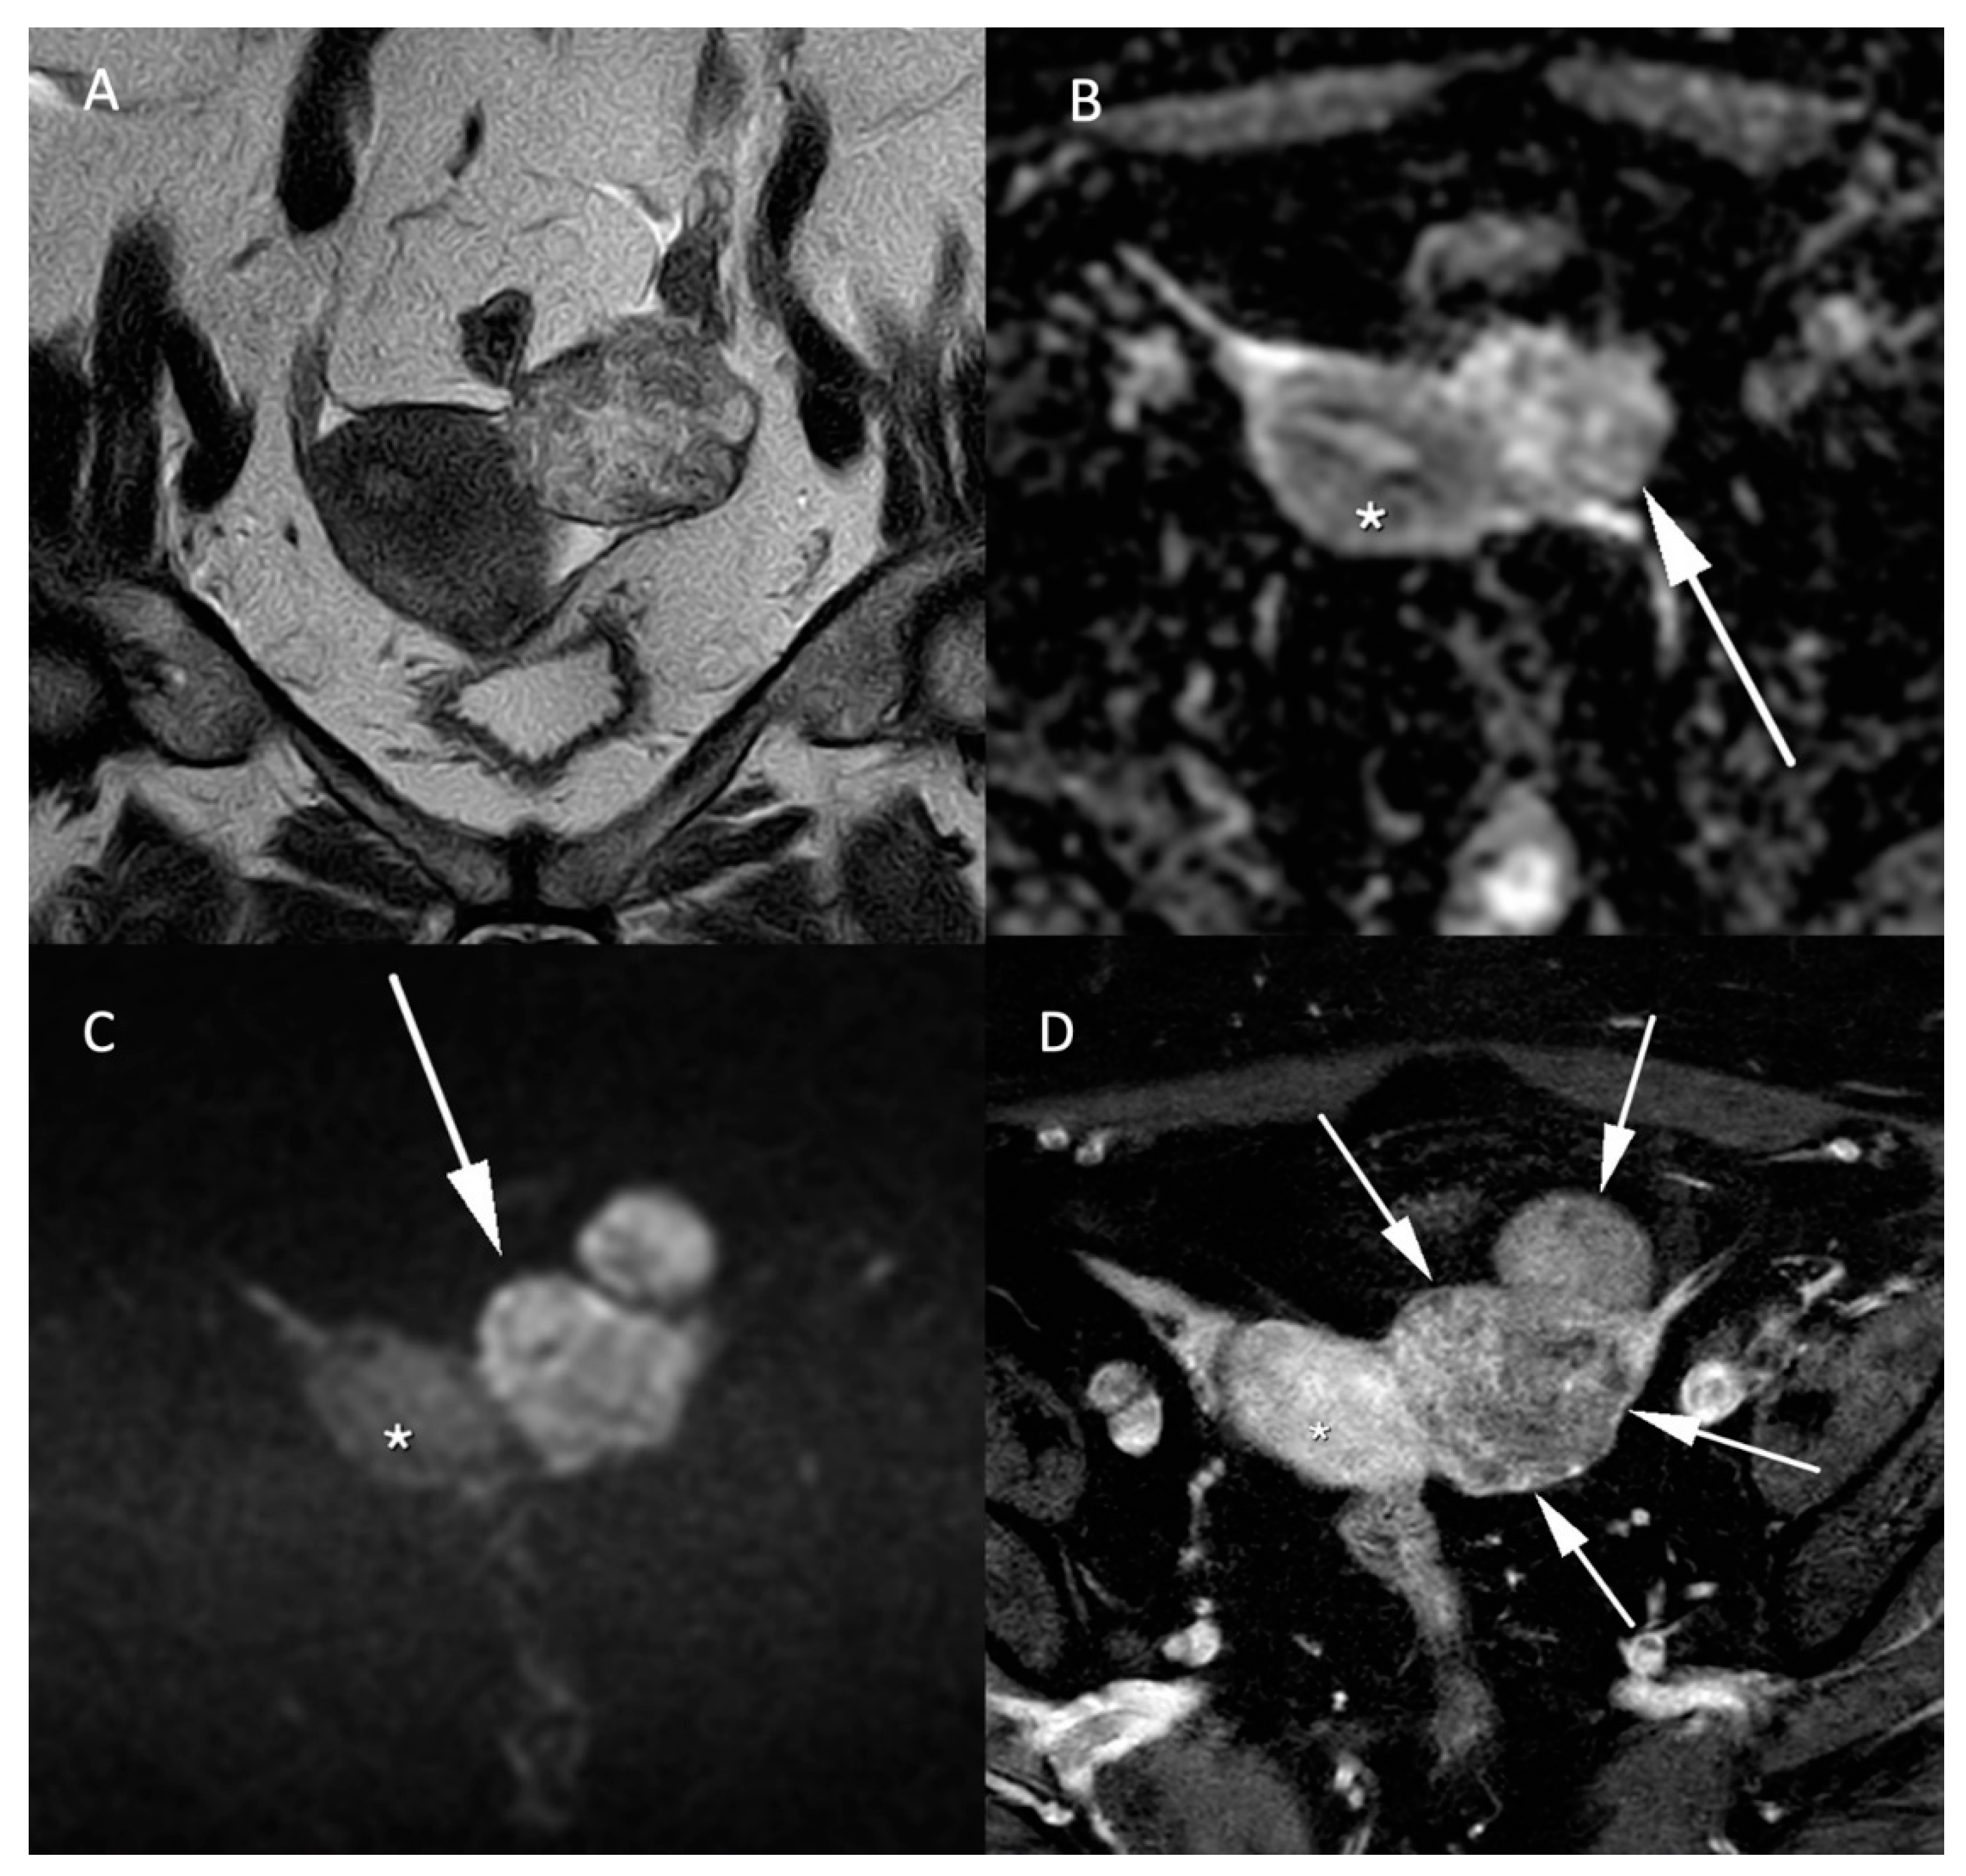

Figure 4.

MR images of a leiomyosarcoma in a 54-year-old woman. (A) voluminous leiomyosarcoma with an intermediary T2W signal and irregular borders (arrow). Part of the leiomyosarcoma demonstrates a diffusion restriction with low (B) ADC values and high signal on the (C) b-1000 sequence. (D) post injection of gadolinium T1W sequence shows the absence of central enhancement consistent with central necrosis. All features are characteristic of malignancy within a leiomyoma.